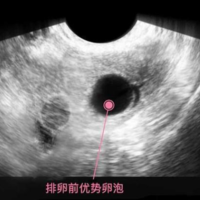

做排卵监测发现只有右侧有一个优势卵泡正常吗?

问题描述:我因为备孕3个月了始终没有怀孕,因此就想去医院做做检查,医生听说我的情况之后着重给我进行了卵巢检查。然后在进行排卵检测项目的时候发现只有右侧有一个优势卵泡,医生虽然没有说什么但我总觉得有问题。有人知道这个现象是否正常吗?最佳回答:做排卵监测发现只有右侧有一个优势卵泡是正常的。在一个月的周期中发育成熟并排卵是正常的生理现象,这是由于女性的卵巢在每个周期中只会释放一个卵子,因此检测到右侧卵巢...